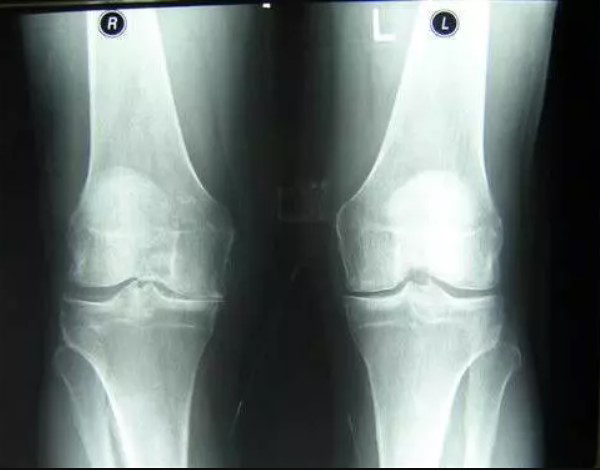

Femme de 54 ans. Son articulation est entièrement restaurée. La durée du traitement : 14 jours :